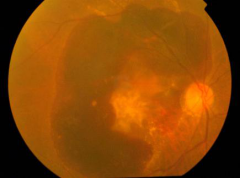

02-02珠海希瑪眼科醫(yī)院:視網(wǎng)膜脫落會有什么后果?能治嗎?

一定要趁早接受檢查,若為視網(wǎng)膜撕裂,在初期及早就醫(yī),珠海?,斞劭漆t(yī)院接診該類患者時,通常采用激光治療法,即在裂孔周圍用激光把裂孔邊燒焊,防止病情惡化,避免視網(wǎng)膜脫...